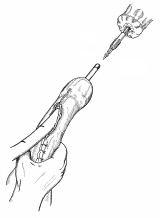

胃全摘術後の再建

器械吻合器を用いた、ρ‐double tract法。